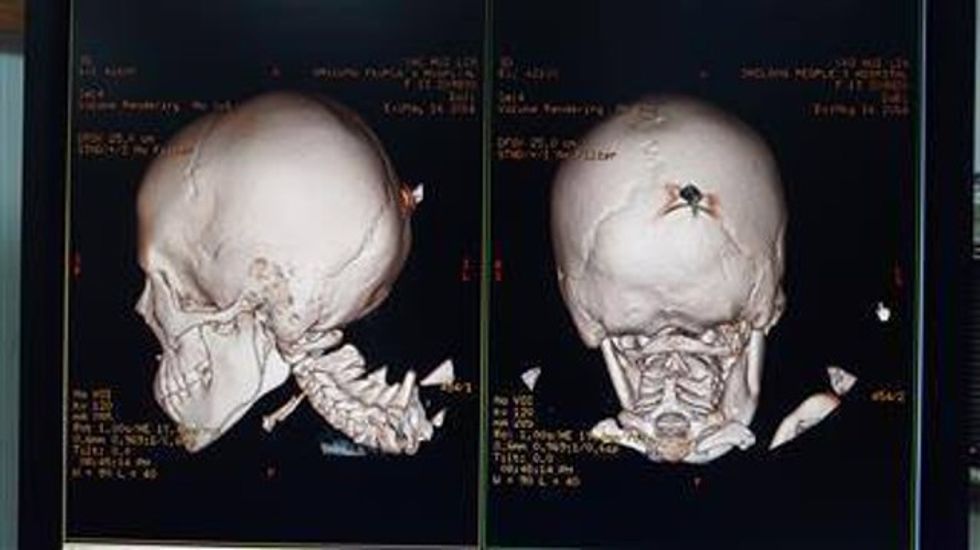

12-vjeçarja arrin në spital me një thikë në kokë (Foto)

Një thikë argjendi 15 cm e gjatë është ngulur dhe ka mbetur në kokën e Linit, 12 vjeçares nga province Guangdong më 16 maj të këtij viti. Ajo u dërgua menjëherë në spital.

Pasi u konsultuan, mjekët vendosën ta mbanin thikën akoma në kokën e saj dhe t’ia hiqnin me ndihmën e mjeteve. Vajza tani është duke u shëruar dhe do të jetë në gjendje të dalë nga spitali së shpejti, transmeton syri.